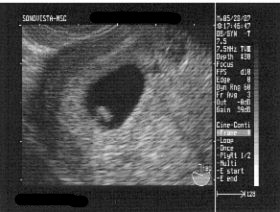

前回、胎嚢の中がからっぽだったのでまだ『おめでとう』の段階ではなかったのですが・・・。

先生「おめでとうございます」

いました!

豆粒が・・・。

隣の部屋で待ってたキャメルも呼ばれ画面を一緒に見ると、先生が示す部分にチカチカ動く部分が。

心臓だって!

全く人の形なんてしてないのにねー。

着衣を整え診察室に行くと超音波の写真を見せてくれました。

お、なんか黒い丸があるよ。

先生曰く、胎嚢(たいのう)があるので妊娠は認められたけどまだ「おめでとう!」の段階ではないそうな。